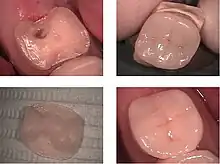

Direct restorations

This technique involves placing a soft or malleable filling into the prepared tooth and building up the tooth. The material is then set hard and the tooth is restored. Where a wall of the tooth is missing and needs to be rebuilt, a matrix should be used before placing the material to recreate the shape of the tooth, so it is cleansable and to prevent the teeth from sticking together. Sectional matrices are generally preferred to circumferential matrices when placing composite restorations in that they favour the formation of a contact point. This is important to reduce patient complaints of food impaction between the teeth. However, sectional matrices can be more technique sensitive to use, so care and skill is required to prevent problems occurring in the final restoration.[5] The advantage of direct restorations is that they are usually set quickly and can be placed in a single procedure. The dentist has a variety of different filling options to choose from. A decision is usually made based on the location and severity of the associated cavity. Since the material is required to set while in contact with the tooth, limited energy (heat) is passed to the tooth from the setting process.